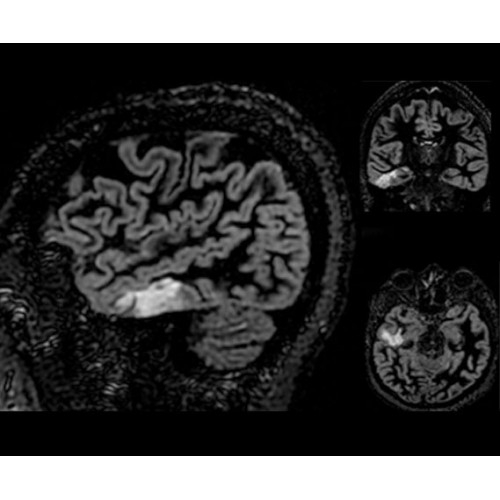

SIGNA Architect 3.0T — это новейший МРТ аппарат компании GE, который предлагает высочайший уровень производительности — в системе 128 приемных каналов, 48 канальная катушка головы, полный спектр клинических возможностей. Высокий уровень комфорта пациента обеспечивают такие особенности как отсоединяемый стол, положение пациента «ногами вперед» для всех видов исследований, SilentWorks — бесшумное и MAGIC — быстрое сканирование.

Теперь возможности МРТ поражают еще больше благодаря ультрасовременным решениям для визуализации с SIGNA Architect 3.0 Тл, объединяющей новейшие достижения в области МР-технологий и интуитивно понятный интерфейс. Система SIGNA Architect, разработанная на базе новой платформы SIGNA Works, представляет собой гармоничное сочетание дизайна и функциональности. Каждый элемент системы направлен на повышение производительности, эффективности клинической практики, финансовых показателей, а также комфорта и безопасности пациента.

• HyperWorks — пакет програмных приложений, который включает технологию HyperSense для поразительной визуализации и скорости.

• ImageWorks — повысит производительность МРТ благодаря визуализации высокого качества с MAGIC, четкими результатами пост-процессинга с READYView.